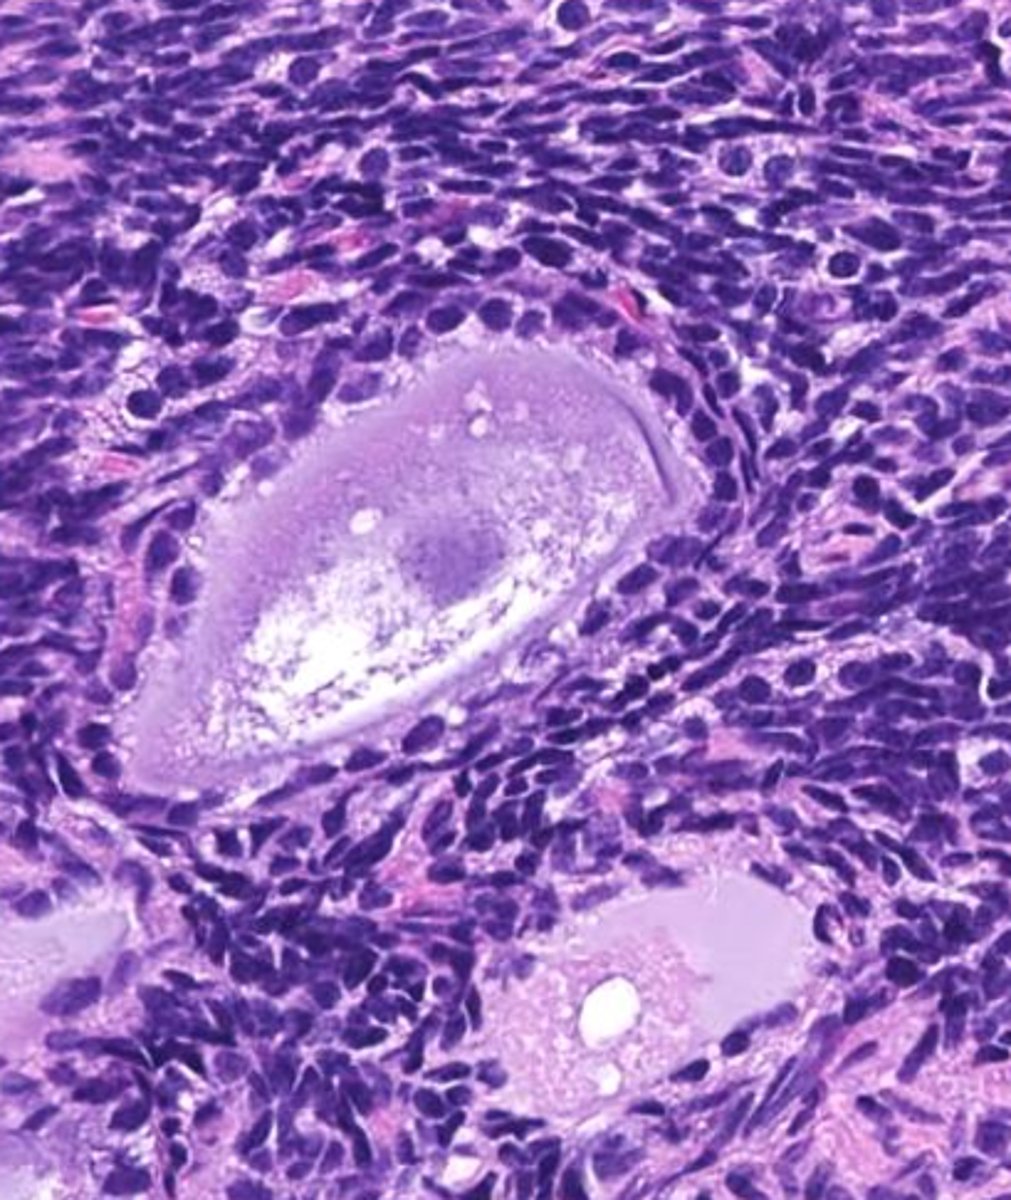

secondary, granulosa, thecal

this is the _____ follicle: As the oocyte develops, the _____ cells proliferate and ______ cells are recruited from the stroma

tertiary

this is a _____ follicle